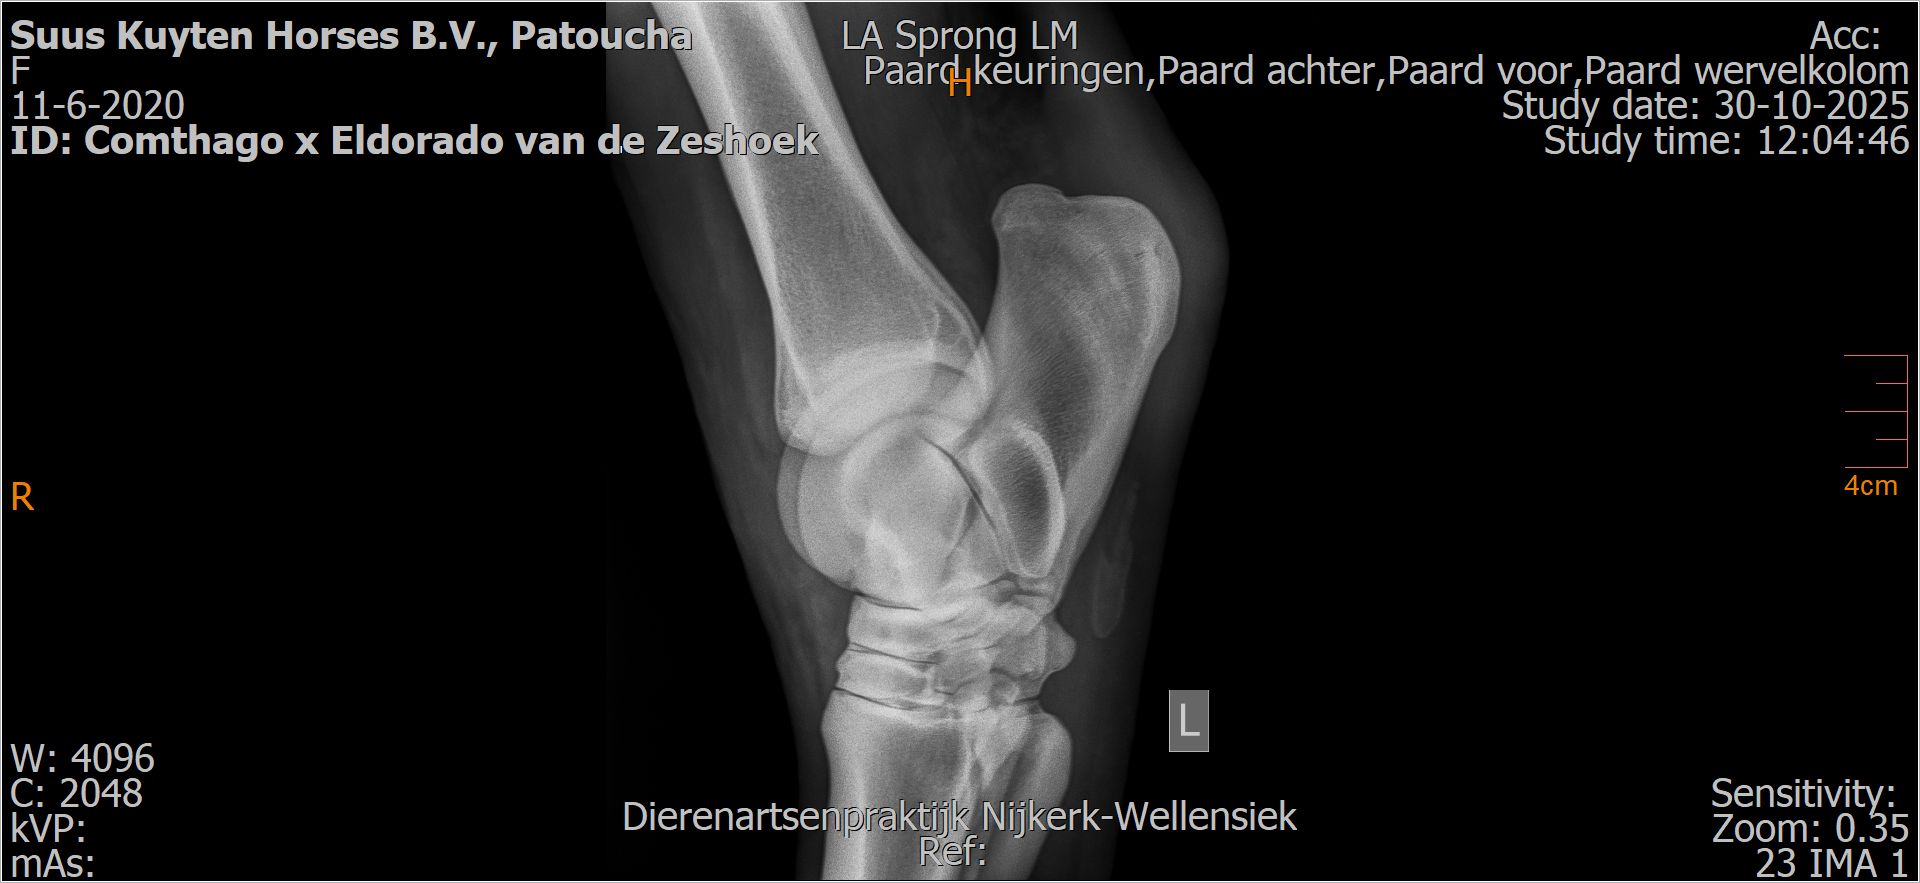

Patoucha

Leeftijd:

7

Röntgenfoto’s